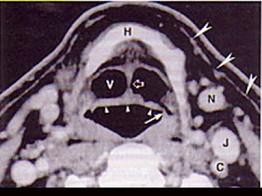

男,55岁,声嘶6年,有长期吸烟史。检查:无呼吸困难。喉镜检查:声带慢性充血,可见右侧声带可见菜花样新生物,右侧声带活动固定,喉部CT检查如下图:诊断...

问题 男,55岁,声嘶6年,有长期吸烟史。检查:无呼吸困难。喉镜检查:声带慢性充血,可见右侧声带可见菜花样新生物,右侧声带活动固定,喉部CT检查如下图: 诊断首先考虑 ( )

答案 D